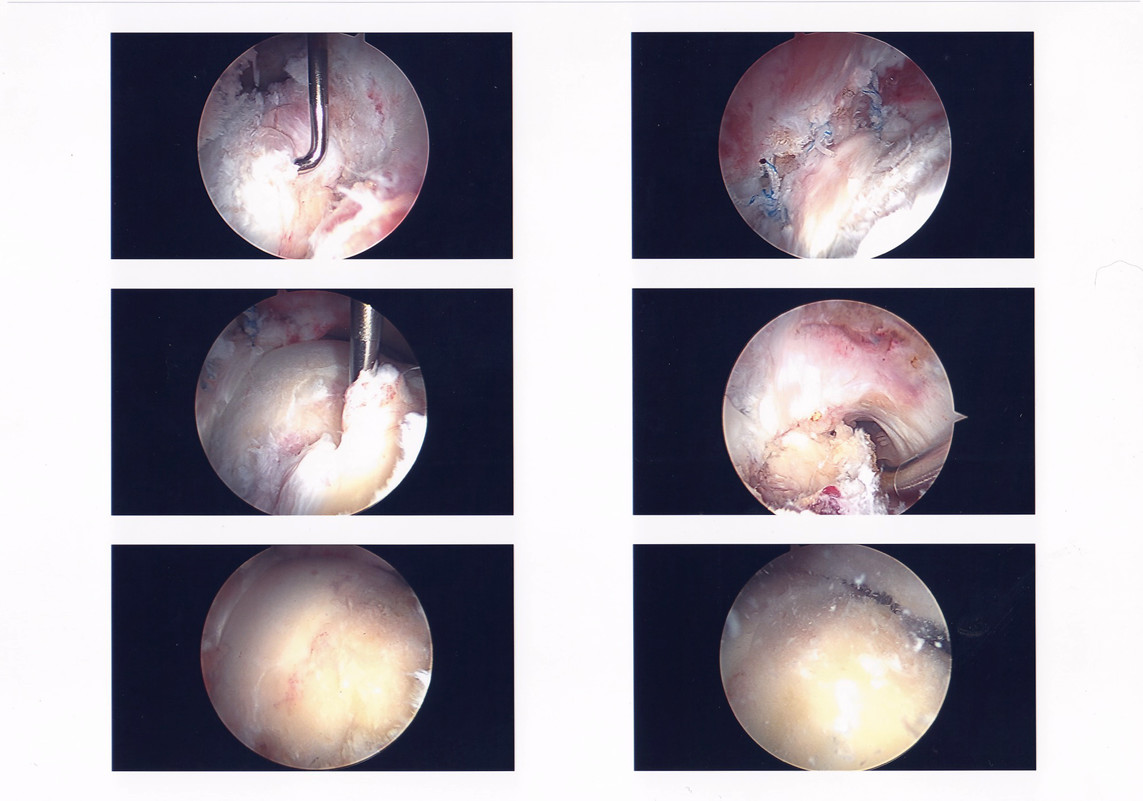

Below is a gallery of the scopes from my surgery. Starting with the initial scope to the Dr. repairing my labrum (if you look at the slide show, it’s the blue thread), then going in and removing the tissue built up in my hip joint and sculpted my hip socket.